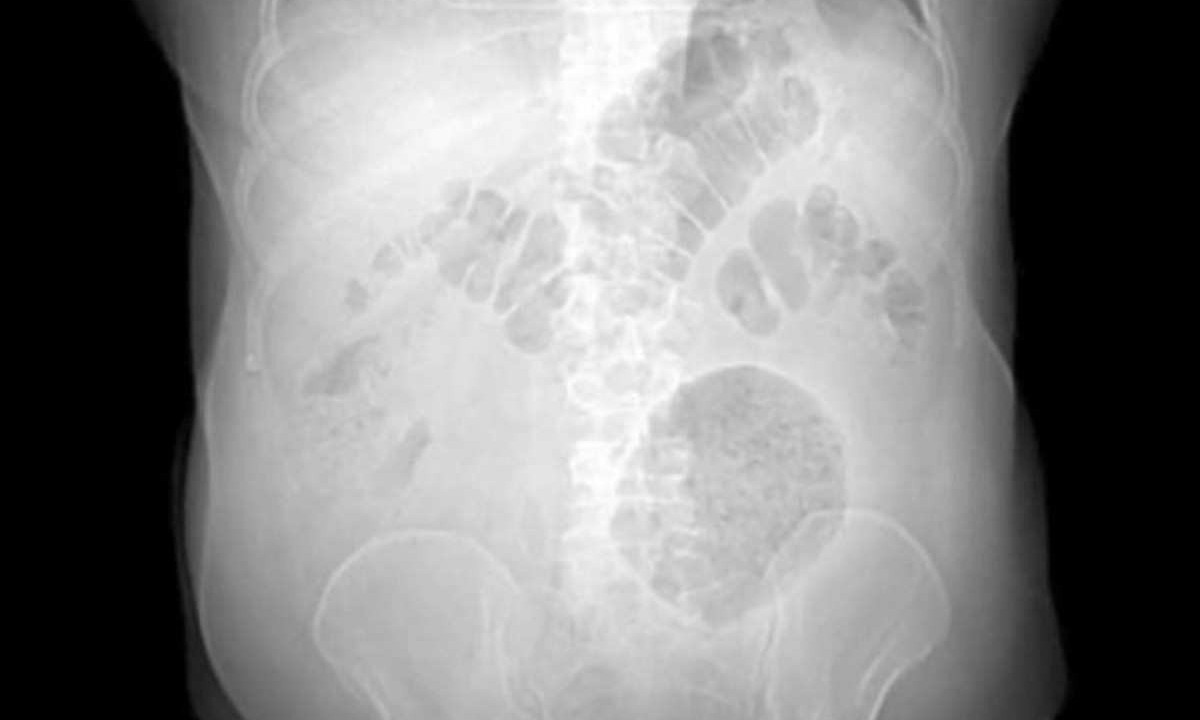

O caso de divertículo gigante chegou pela emergência do hospital. O paciente vinha sofrendo de dores abdominais e perda de peso há pelo menos dois meses. O Hospital Municipal Salgado Filho, no Rio de Janeiro, identificou um caso de doença raríssima, com menos de 200 relatos catalogados pela literatura médica até hoje: o divertículo gigante do cólon (DGC). Segundo a Secretaria Municipal de Saúde, o paciente, um homem de 62 anos, foi operado e está plenamente recuperado. A doença raríssima é uma formação inflamatória de 13 x 12 x 10cm na região abdominal. Em média, este tipo de inflamação tem entre 4cm e 9cm de diâmetro. O caso identificado no Rio de Janeiro foi apresentado no 17° Congresso Europeu Colorretal, realizado entre os dias 3 e 6 de dezembro de 2023, na cidade de St. Gallen, na Suíça. O caso de divertículo gigante chegou pela emergência do hospital. O paciente vinha sofrendo de dores abdominais e perda de peso há pelo menos dois meses. Um exame clínico indicou a presença de uma massa flácida, palpável e dolorosa no flanco esquerdo do abdômen. Ao ver o resultado da tomografia computadorizada, o médico cirurgião Leonardo Fiuza ficou incrédulo com o tamanho da inflamação. “Nunca tínhamos ouvido falar em divertículo gigante. Pesquisamos e vimos que os casos eram raríssimos. Foi uma surpresa muito grande, que começou com um paciente com queixa de dor na barriga. Ficamos muito orgulhosos pelo fato de o Hospital Salgado Filho ser representado na Suíça, com um trabalho superinteressante sobre um caso tão raro”, comentou o médico.

De acordo com a Sociedade Brasileira de Hepatologia, o divertículo gigante do cólon afeta homens e mulheres igualmente e a faixa etária de maior incidência é entre 35 e 90 anos (média de 65 anos). “Os exames de imagem, como raio-X simples de abdômen, tomografia computadorizada, ressonância magnética e enema opaco, são de grande valor diagnóstico, enquanto a colonoscopia não apresenta benefício na investigação desta doença. O tratamento cirúrgico é o de escolha devido ao grande potencial de complicações que esta patologia apresenta”, diz a instituição.